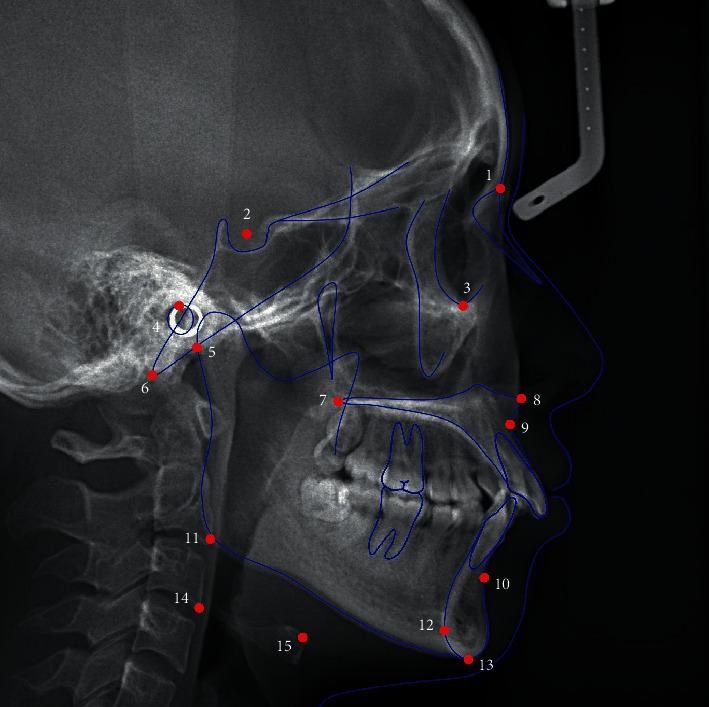

The present cross-sectional study was conducted in 427 participants whose osseous status was evaluated using cone-beam computed tomography and classified into normal, indeterminate osteoarthrosis (OA), and OA. The hyoid bone position and craniofacial characteristics were evaluated using cephalograms. Patients were divided into the normal group ( = 89), indeterminate OA group ( = 182), and OA group ( = 156). Descriptive statistics, one-way analysis of variance, and age- and sex-based stratified analyses were performed. < 0.05 was considered statistically significant.

The differences in Hy to MP, Hy-RGn, Hy to C3-RGn, C3-RGn, and Go-Hy-Me among the three groups were statistically significant. The differences in the Frankfort-mandibular plane angle, saddle angle, articular angle, gonial angle, ramus height, and posterior facial height were statistically significant. After adjusting age and sex, the Hy-RGn and C3-RGn in the normal group were significantly greater than the OA group. No statistical differences were observed in the hyoid measurements in the stratified analyses in males or subjects less than 18 years old. The differences in Hy to MP, Hy to C3-RGn, and Go-Hy-Me in female patients among the three groups were statistically significant. The differences in Hy to SN, Hy to FH, Hy to PP, Hy to MP, Hy-RGn, Hy-C3, Hy to C3-RGn, Go-Hy-Me, Hy-S, and C3-Hy-S in adults were statistically significant.